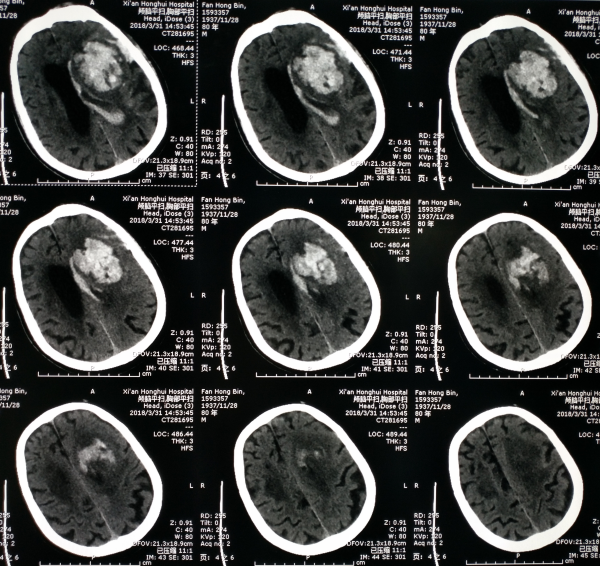

80岁老人突发昏迷伴右侧肢体偏瘫2小时入院。头部CT提示左侧基底节出血破入脑室,出血量约80毫升。

术后精心管理病人,病情一直比较平稳。术后20天复查头部CT见颅内积血完全吸收,给予促醒治疗,术后50天病人清醒。